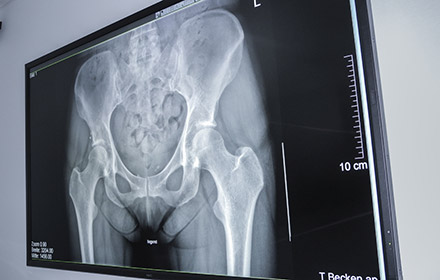

The Merian Iselin Hospital for Orthopaedics and Surgery is one of three large private hospitals in Basel, Switzerland and nationwide one of the houses with the largest number of surgical interventions in knee and hip surgery. The most important centre piece of the hospital is the radiology department, which creates imaging reports for both external and in-house physicians. More than 20,000 radiological examinations were carried out here in 2014.

Common diagnostic monitors were not suitable for this purpose, as they are far too small for larger groups of people to gather around. Previously used large-format display technologies offered only lower resolutions and therefore could not display detail with the precision nor colour nuances required. The hospital was seeking a new solution, one which would meet their requirements for resolution, colour quality and signal processing in UHD quality, whilst impressing on patients and physicians that they are a meticulous care provider.

The extreme detail achieved with the UHD resolution display permits more precise diagnoses and allows extremely low viewing distances. Medical image data is reproduced correctly thanks to precise calibration and DICOM mode. “Black is really shown as black, just like white is really white on the screen”, says Dr. Egelhof with delight. A semi-matt surface restricts the effect of reflections on the screen.

“The Merian Iselin Hospital offers its customers and patients best service and highest quality. Therefore, the requirements which the hospital imposes on itself, also apply to the technical equipment”, says Christoph Kreutner, Technical and IT Manager of the hospital. “The discussion of the x-rays is now possible for the first time at the highest level, as the image can now be shown in the same quality and grade as on the diagnostic monitor.”